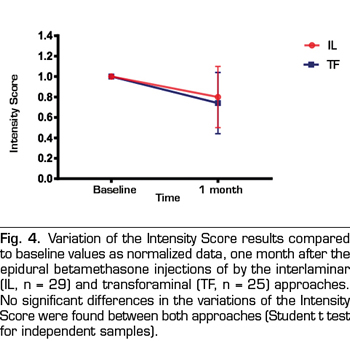

Intensity and Interference Scores were also reduced by the epidural steroid injection (Figures 4 and 5). Betamethasone administered by the parasagittal interlaminar approach produced a statistically significant reduction of the Intensity Score from 7.2 ± 1.2 to 5.8 ± 2.1 and the Interference Score from 7.0 ±1.8 to 5.8 ± 2.5 (p = 0.002 and p = 0.01, respectively; Student t test of paired samples). Betamethasone administered by the transforaminal route decreased the Intensity Score from 7.7 ± 1.6 to 5.7 ± 2.4 and the Interference Score from 7.7 ± 1.7 to 6.3 ± 3, statistically significant reduction (p = 0.0002 and p = 0.008, respectively). No statistically significant differences were found between both approaches when comparing the reduction of both scores.